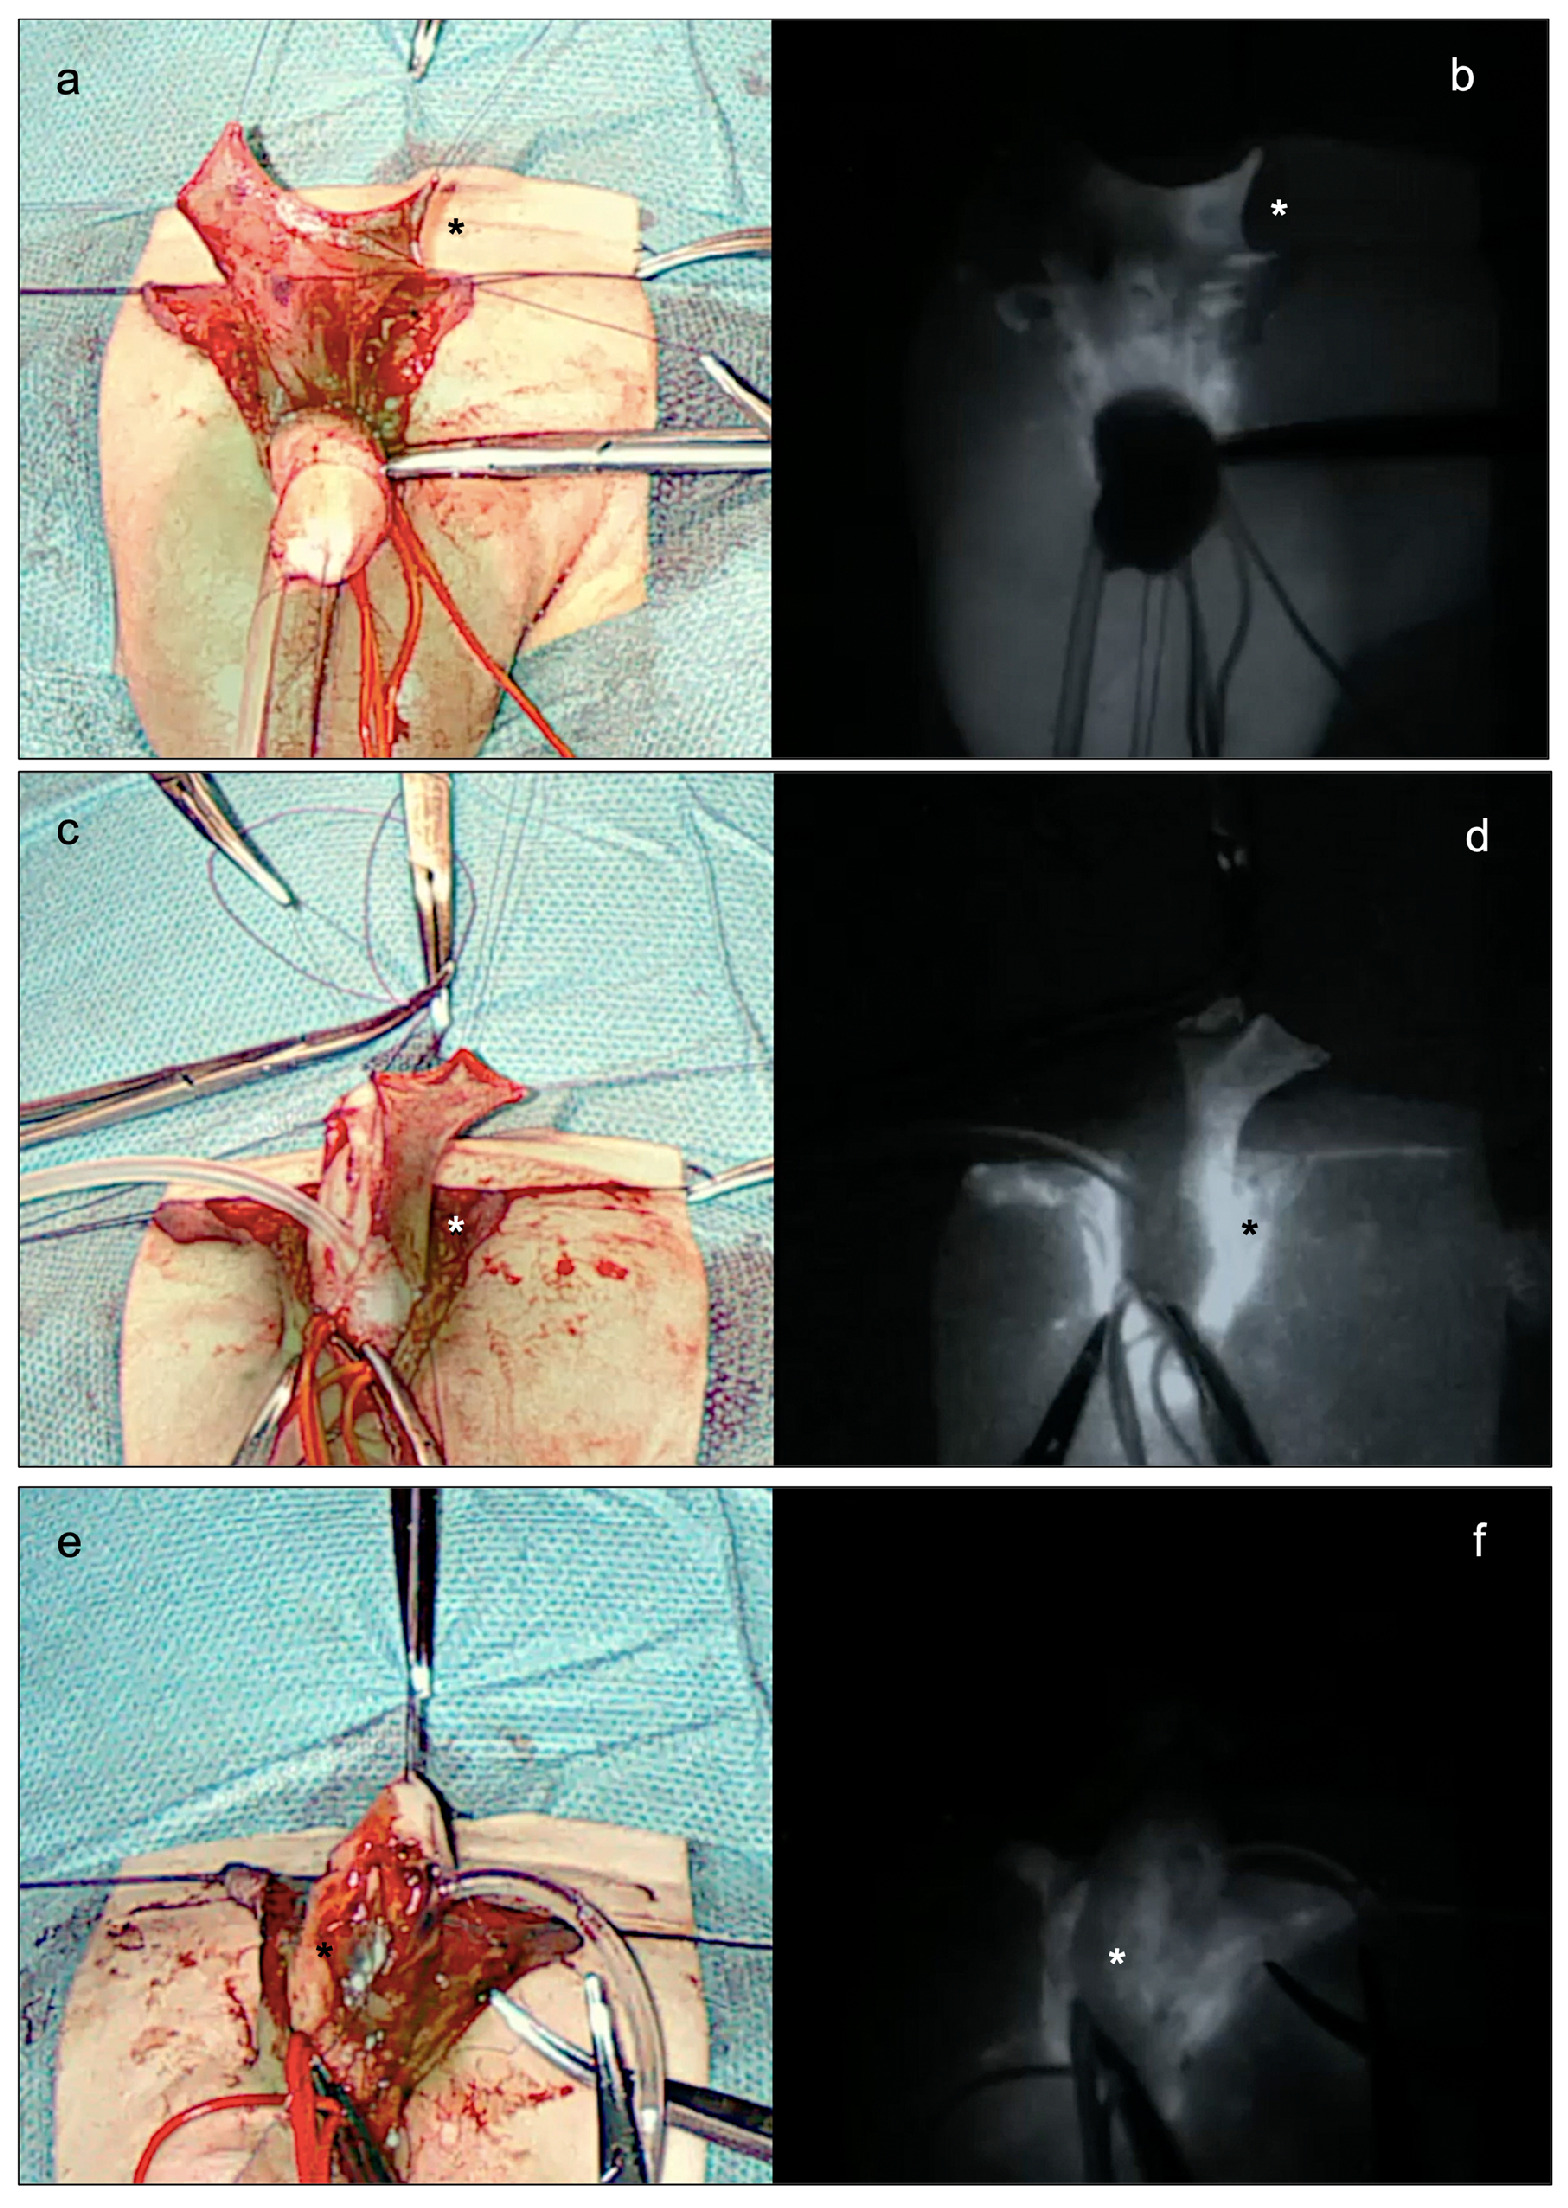

As the standard onlay preputial island flap urethroplasty, the procedure began with the demarcation of the urethral plate and the catheterization of the mid-shaft meatus (Figure 2a). Following the application of a tourniquet at the base of the penis for maintaining a bloodless field, the penis was degloved, preserving the urethral plate. An artificial erection test was then performed, which showed no ventral penile curvature (Figure 2b). After measuring the length of the urethra to be reconstructed, a transverse preputial island flap of suitable length (i.e., 35 mm) was then prepared (Figure 2c). At this point, 0.15 mg/kg of ICG (Diagnostic Green GmbH, Munich, Germany) was administered, and the EleVision IR system (Medtronic Ltd.) was incorporated to help assess the perfusion of the preputial island flap in real-time. The aim of their employment during surgery was to reduce the complications associated with a poorly vascularized preputial flap (Figure 3). Favorable fluorescence was obtained 80 s after the injection, confirming the proper vascularization of the onlay preputial island flap elevated on its pedicle, especially on its proximal left side (Figure 3a,b). Hence, the ICG-based navigation system applied to the surgical field helped define the proximal resection margin, and guided the excision of the distal part, significantly impacting the intraoperative decision-making (Figure 3c,d).

The preputial island flap was then placed as an onlay over an 8 Ch catheter, to create the neo-urethra. Again, the perfusion of the ventral part of the neo-urethra was assessed by using the EleVision IR system (Medtronic Ltd.), and proved to be adequate (Figure 3e,f). A single-layer glanduloplasty and skin closure followed, as in standard onlay repairs (Figure 1b).

Figure 3. Main steps of the indocyanine green (ICG)-guided onlay preputial island flap urethroplasty in a 13-month-old boy referred to our tertiary referral hospital for a mid-shaft hypospadias. (a,b) Assessment of the vascular supply (*) of the transverse preputial island flap elevated on its pedicle, 80 s after the injection of 0.15 mg/kg of ICG (Diagnostic Green GmbH, Munich, Germany) and the incorporated the EleVision IR system (Medtronic Ltd.) on the surgical field. (c,d) Assessment of the vascular supply (*) of the transverse preputial island flap transposed ventrally and sewn to the margins of the urethral plate. (e,f) Assessment of the vascular supply (*) of the ventral part of the neo-urethra.